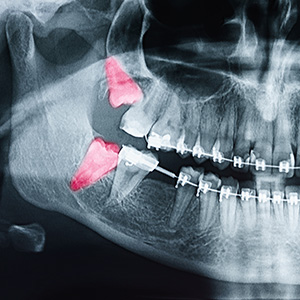

At Cranberry Oral Surgery, Dr. Daniel J. Kirkpatrick, DDS, and his dedicated team are committed to providing the highest quality care in a compassionate and comfortable environment. Our practice offers a full spectrum of oral and maxillofacial surgery services, including wisdom tooth removal, and the treatment of facial pain and injuries. We also specialize in dental implant placement and bone grafting procedures, using advanced techniques to ensure optimal results for our patients.